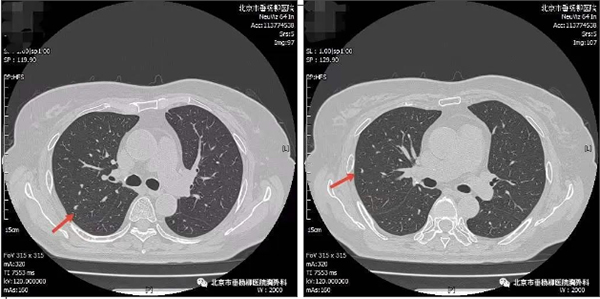

【垂医病例科普】肺结节:相似的外表,不…